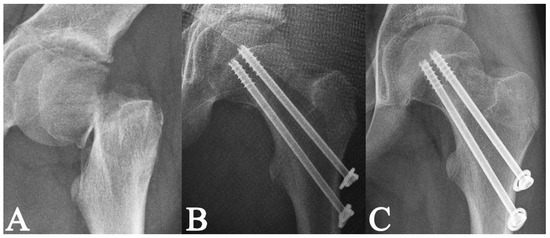

2. Materials and Methods